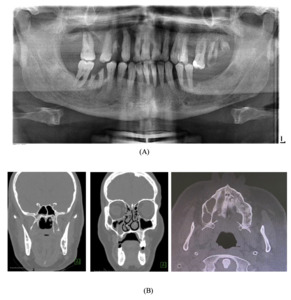

A pre-operative orthopantomogram (OPG) showed multiple non-restorable teeth in both jaws, as well as generalised, horizontal moderate to severe bone loss (Figure 2a). Pre-operative cone beam computed tomography (CBCT) showed an ill-defined lesion on the palatine process of the right maxillary and alveolar bone (Figure 2b).